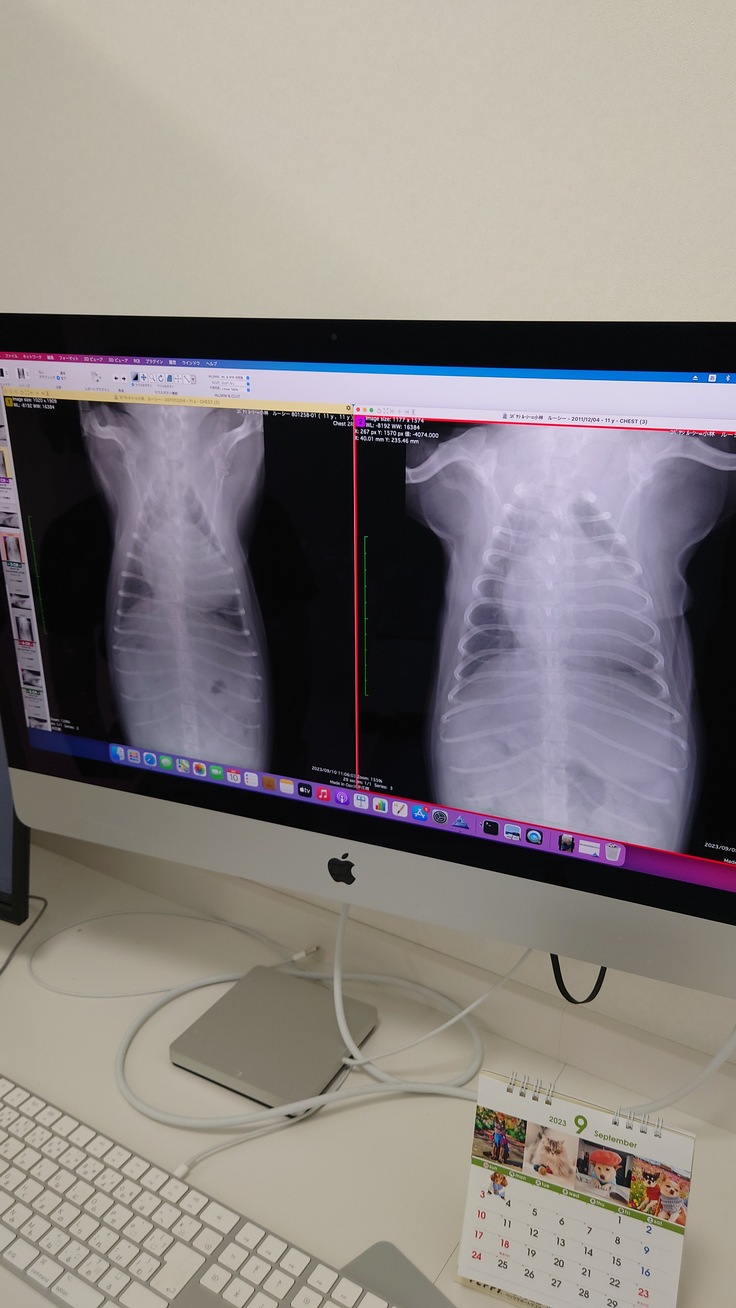

右が入院前の肺、左が今日の朝の段階での肺の状態です。

白い部分が水が入っている部分になりますが、

明らかに今朝のほうが黒い部分が多くて、

肺に水が溜まっていないのがわかります。

今まで使っていたプロセミドよりも強めの利尿剤(薬品名失念しました)

が効果があったみたいで、

退院しても良い状態が近いそうです。